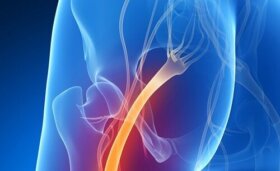

하부 요통은 흔한 증상이다. 사실 류머티즘 질병 연보에 발표된 연구는 하부 요통이 가장 치명적인 병이라는 사실을 일깨워 준다. ‘치명적’이라는 말은…

쉽게 진단이 되는 건강 문제들이 있다. 하지만 좌골 신경통처럼 다른 문제들과 증상을 착각할 수 있는 질병들도 있다. 계속 읽어가면서 좌골 신경통이 있는지…